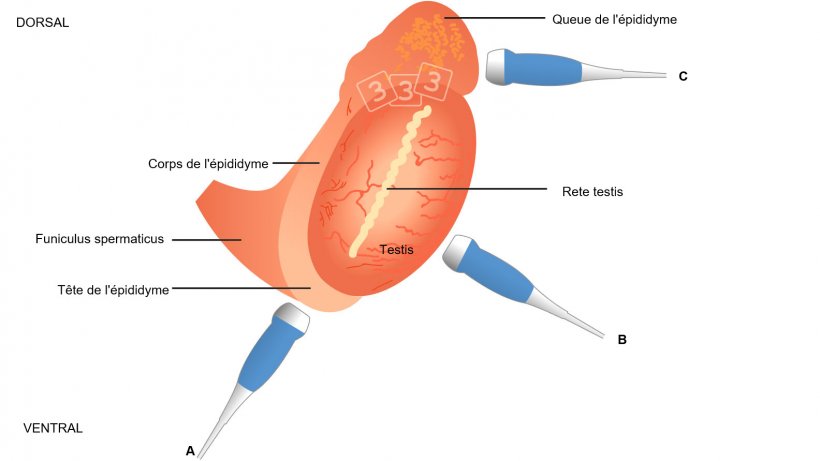

L'examen des glandes sexuelles accessoires doit être fait par voie transrectale en utilisant une sonde linéaire (Clark et Althouse, 2002; Figure 1), tandis que pour le testicule, l'épididyme et le cordon spermatique, un secteur ou sonde (micro) convexe est le type de dispositif préféré (figures 2A et B). On utilise des fréquences de 5,0 à 9,0 MHz, les plus basses étant les plus appropriées pour la plupart des tissus qui nécessitent une plus grande profondeur de pénétration (à savoir le testicule et le corps de l'épididyme) et les fréquences plus élevées pour les structures plutôt petites comme la tête et la queue de l'épididyme). Cela dépendra donc de l'objectif de l'examen et la fréquence sera alors optimale.

Figure 2: Procédure de scan du testicule d'un verrat calme sans contention, après l'éjaculation dans la salle de collecte de semence. A) Exploration longitudinale au moyen d'une sonde micro-convexe . B) Exploration transversale en utilisant une sonde convexe. Ce type d'exploration doit aussi être utilisée pour visualiser le corpus epididimis.

Le scann de l'épididyme doit être fait aussi dans différentes positions en fonction de la zone d'intérêt. Pour la tête il faut travailler ventralement; pour le corps transversalement au milieu de l'axe horizontal du testicule tout le en maintenant manuellement; pour la queue on réalise un scann dorsal en poussant manuellement le testicule et l'épididyme dorsalement (Figure 4, Kauffold et al., 2011).